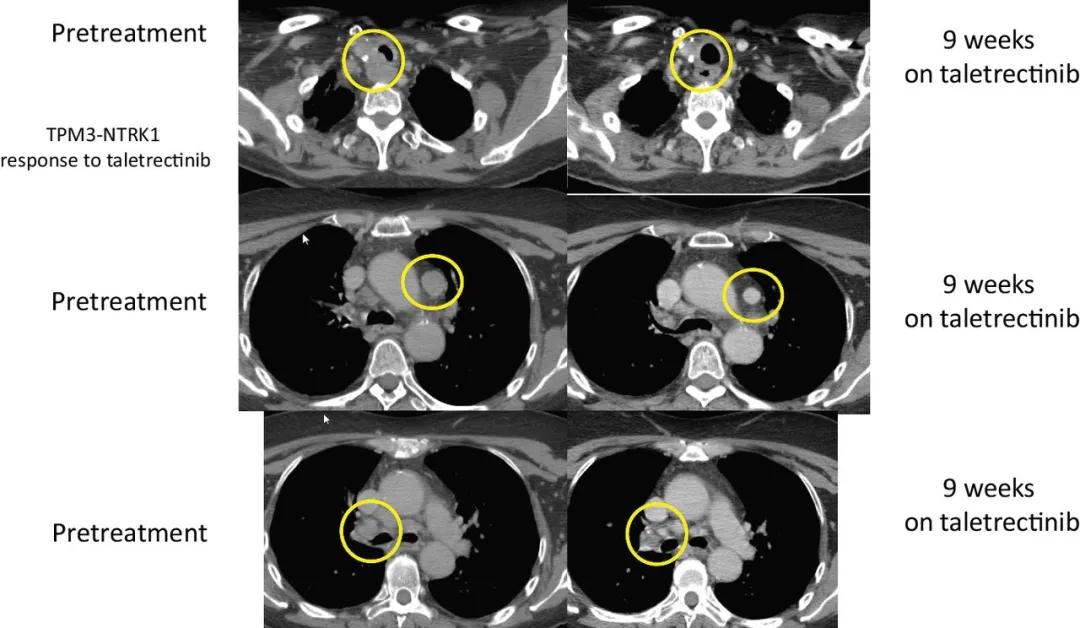

另一位患者是晚期甲状腺癌,手术后接受了化学放疗,放射性I-131,索拉非尼,以及PD-1的临床试验,后经过Foundation One CDx检测到存在TPM3-NTRK1 融合,参加了taletrectinib的临床试验,截止到文献发表,这名幸运的患者持续缓解时间已经长达33.4个月,将近3年。